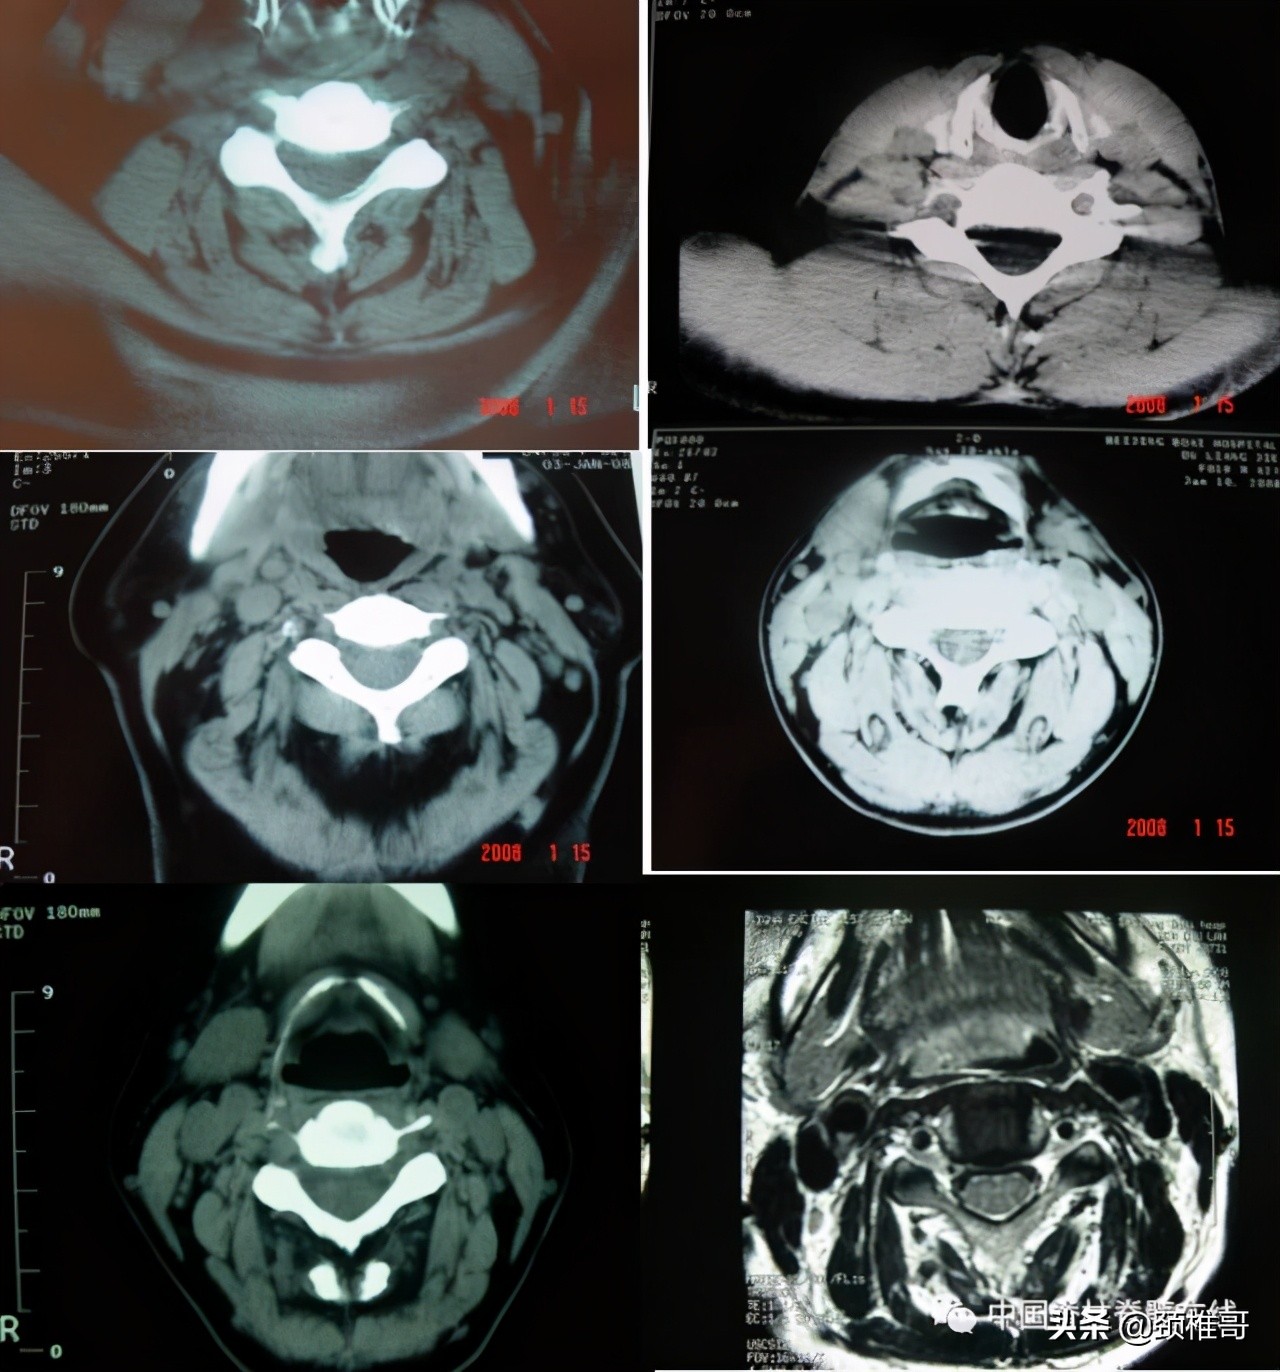

3、典型病例三:椎间盘膨出椎间不稳代偿性增生的交感神经型颈椎病患者

另外一个例子,这是一个头晕8年的病人,他的颈椎核磁共振显示,颈椎3-6各个节段之间的椎间盘退变膨出,局部有一些骨质增生,但没有明显的神经受压,横断面扫描显示颈椎周围肌肉有严重的退变表现;在X线检查时发现,棘突排列顺序不佳,颈4/5椎体之间有台阶,颈椎3-7各个节段之间夹角增大,都超过了11度;过屈位显示颈2-4椎出现了双边征,是旋转不稳的表现。这个病人的椎间盘虽然已经出现了退变、膨出,并发生了骨质增生,对硬膜囊产生了轻度压迫。但是其主要问题是椎间盘退变吗?不对,其主要问题还是多节段的椎间不稳,既有夹角增大,又有台阶,还有旋转。导致此病人头晕的主要原因还是肌肉和韧带的控制能力的下降所导致的。

正位显示椎体序列不佳、侧位显示颈椎4/5之间台阶状改变

过伸过屈侧位X线片显示多节段颈椎不稳

在椎间盘膨出、颈椎不稳基础上发生的代偿性增生